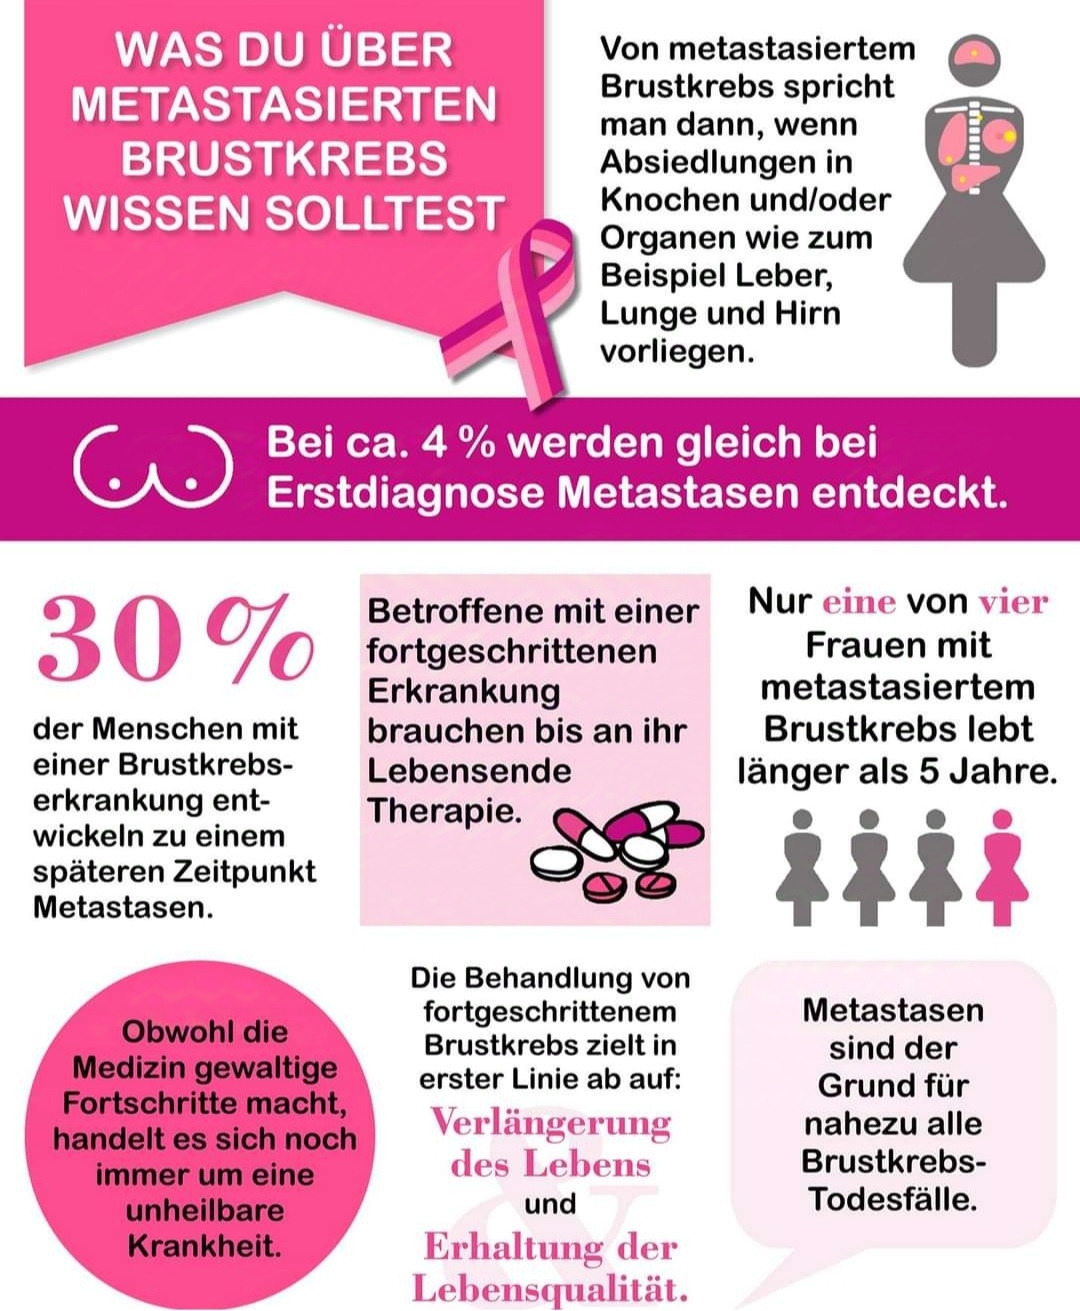

Doch im Frühjahr 2024 kam der Schock: metastasierter Brustkrebs, offiziell palliativ – unheilbar.

Aber Sandra gibt nicht auf. Sie glaubt – und ich glaube mit ihr – dass das nicht das Ende sein muss.

In den letzten Jahren hat sich in der Krebsforschung unglaublich viel getan. Es gibt neue, hochmoderne Therapien, die das Leben verlängern und manchmal sogar den Verlauf verändern können.